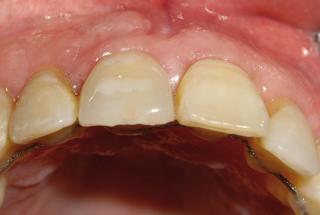

Clinical cases

MPI closely monitors clinical cases in the market to ensure their correct functioning and successful outcome.